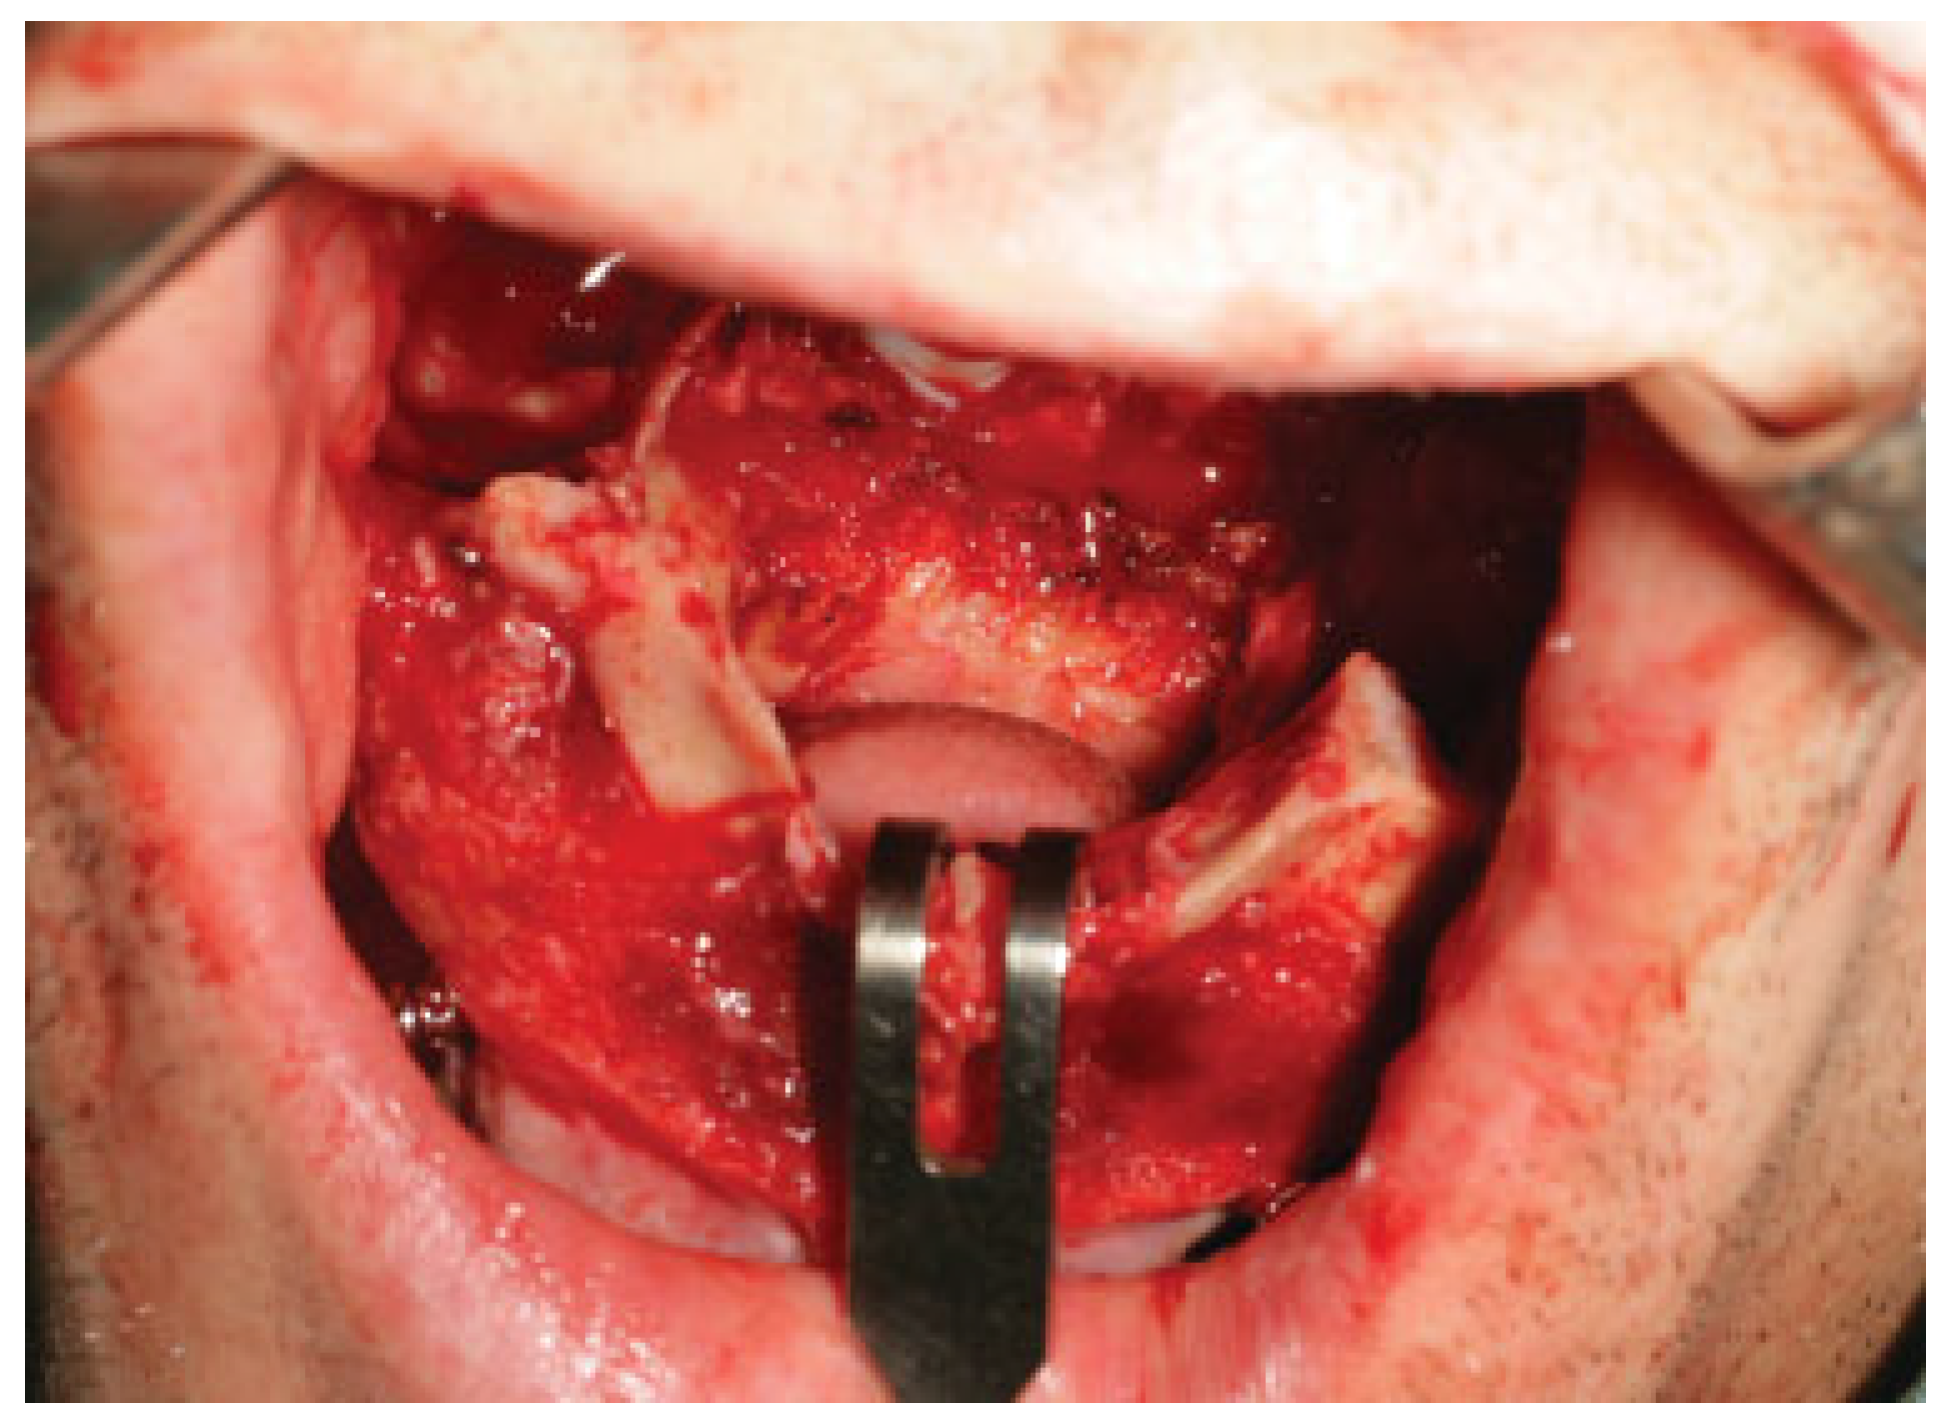

Once the osteotomy is completed, the maxilla is downfractured progressively ensuring that the tumor is completely detached from the rest of the maxilla (Figure 3). Finally, the tumor resection is completed by direct visualization of all the margins (Figure 4 and Figure 5). Before the maxilla is repositioned, the nasal lining closure is accomplished. For this purpose, the authors choose to use vomer or turbinate flaps when direct closure could not be achieved.

Figure 3. A Le Fort I osteotomy is done and the maxilla is down-fractured to complete the tumor resection.